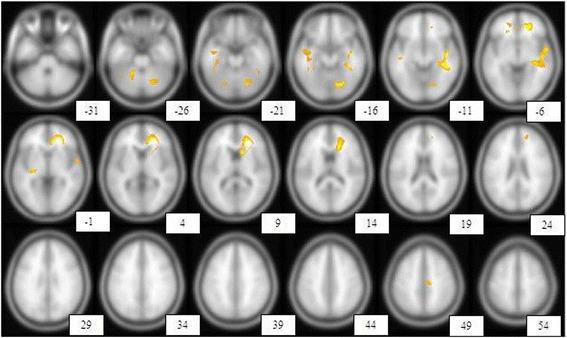

METHODS

We retrospectively reviewed 25 secondary progressive (SP)-MS patients from the hospital database. Neurological disability evaluated by Expanded Disability Status Scale Score (EDSS). Brain perfusion was performed by (99 m) Tc-labeled bicisate (ECD) brain SPECT and the data were compared using statistical parametric mapping (SPM). In total, 16 patients underwent HBOT. Before HBOT and at the end of 20 sessions of oxygen treatment, 99mTc-ECD brain perfusion single photon emission computed tomography (SPECT) was performed again then the results were evaluated and compared. Brain perfusion was performed by (99 m) Tc-labeled bicisate (ECD) brain SPECT and the data were compared using statistical parametric mapping (SPM).

RESULTS

A total of 25 SP-MS patients, 14 females (56 %) and 11 males (44 %) with a mean age of 38.92 ± 11.28 years included in the study. The mean disease duration was 8.70 ± 5.30 years. Of the 25 patients, 2 (8 %) had a normal SPECT and 23 (92 %) had abnormal brain perfusion SPECT studies. The study showed a significant association between severity of perfusion impairment with disease duration and also with EDSS (P <0.05). There was a significant improvement in pre- and post-treatment perfusion scans (P <0.05), but this did not demonstrate a significant improvement in the clinical subjective and objective evaluation of patients (P >0.05).